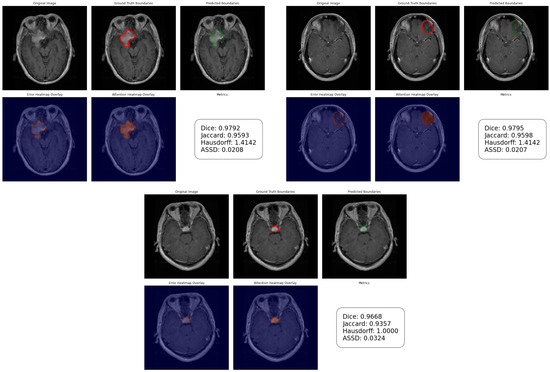

Multi-Scale Atrous Feature Fusion Based on a VGG19-UNet Encoder for Brain Tumor Segmentation

by Shoffan Saifullah and Rafał Dreżewski

Appl. Sci. 2026, 16(8), 3971; https://doi.org/10.3390/app16083971 - 19 Apr 2026

Accurate brain tumor segmentation from magnetic resonance imaging (MRI) remains challenging due to heterogeneous tumor morphology, intensity variability, and multi-scale structural complexity. This study proposes a DeepLabV3+-based segmentation framework integrating a VGG19-UNet encoder, Atrous Spatial Pyramid Pooling (ASPP), and low-level feature refinement to [...] Read more.

Accurate brain tumor segmentation from magnetic resonance imaging (MRI) remains challenging due to heterogeneous tumor morphology, intensity variability, and multi-scale structural complexity. This study proposes a DeepLabV3+-based segmentation framework integrating a VGG19-UNet encoder, Atrous Spatial Pyramid Pooling (ASPP), and low-level feature refinement to simultaneously capture hierarchical semantics and boundary-sensitive spatial details. The architecture enhances receptive field coverage without additional downsampling while preserving fine-grained contour information during reconstruction. Extensive evaluation was conducted on the Figshare Brain Tumor Segmentation (FBTS) dataset and the BraTS 2021 and BraTS 2018 benchmarks, focusing on Whole Tumor segmentation across multiple MRI modalities and tumor grades. Under five-fold cross-validation, the proposed model achieved a mean Dice Similarity Coefficient of 0.9717 and Jaccard Index of 0.9456 on FBTS, with stable and competitive performance across FLAIR, T1, T2, and T1CE modalities in both HGG and LGG cases. Boundary-level analysis further confirmed controlled Hausdorff Distance and low Average Symmetric Surface Distance. Statistical validation and ablation analysis demonstrate consistent improvements over baseline U-Net configurations. The proposed framework provides a robust and computationally efficient solution for automated brain tumor segmentation across heterogeneous datasets. Full article